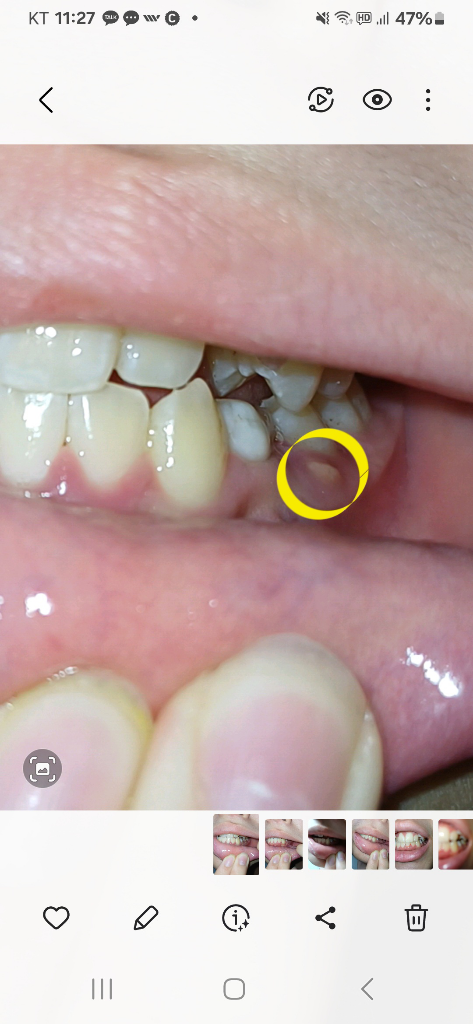

하지만 사진으로 봤을 경우에는 유치의 뿌리 쪽에 염증이 생겨서 고름이 차이는 것으로 보입니다.

이런 경우에는 유치를 발치를해주는 것이 좋으며 발치를 했을 때는 매복되어 있는 치아를 맹출 시키거나 보철 치료 등으로 치아가 없는 부위를 수복해 주는 것이 좋습니다.